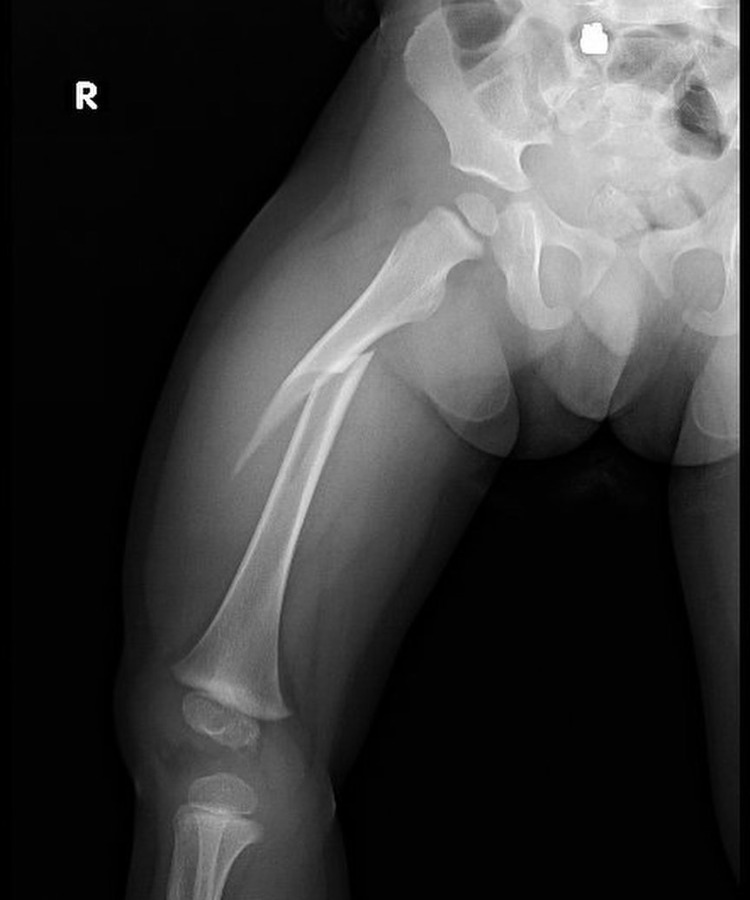

Las fracturas en niños son comunes y pueden afectar su crecimiento si no se tratan debido a las características únicas de sus huesos en desarrollo.

Las deformidades de pie y rodilla incluyen genu varo, genu valgo, pie plano y pie cavo, con causas congénitas o postraumáticas.